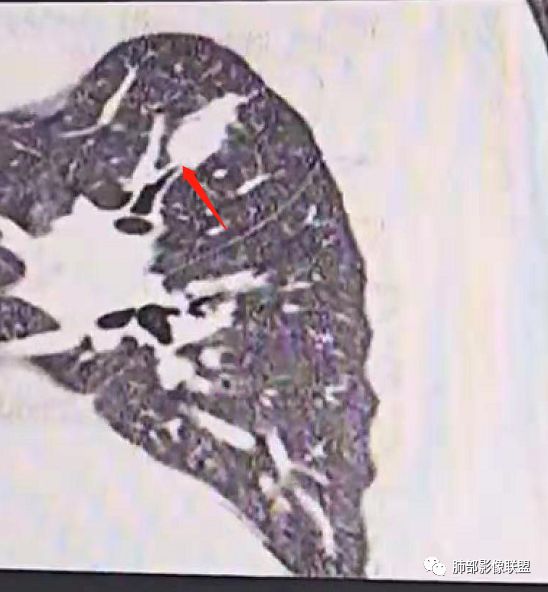

内部小点状影提示可能支气管腔内粘液栓

遗憾的是:层厚太厚,无重建

因此我们需要的是:薄层、重建,看GGO边缘、看整体形态

瘢痕癌就需要薄层、重建观察更妥当

南边:瘢痕癌就需要薄层、重建观察更妥当

结果:结核合并真菌(曲霉菌)感染